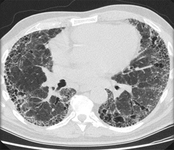

Chest CT with presence of signet ring on left in a patient with bronchiectasis

From the personal collection of Dr S.M. Bhorade, University of Chicago Medical Center

Chest CT with dilated and thickened airways and peripheral tree-in-bud pattern in a patient with bronchiectasis

From the personal collection of Dr S.M. Bhorade, University of Chicago Medical Center; used with permission